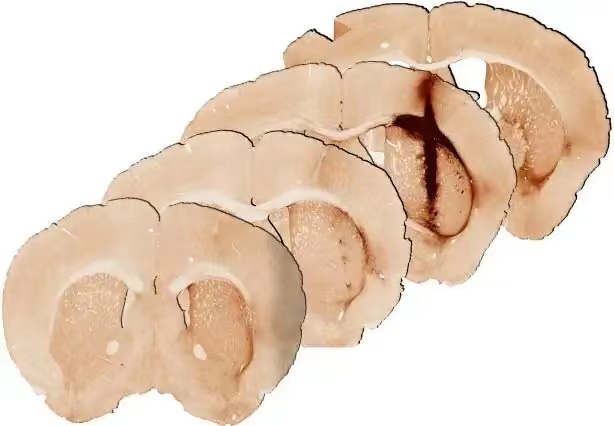

与注射不含肌红蛋白的水凝胶相比,注射含肌红蛋白的水凝胶的小鼠脑组织显示出更为健康的状态。图片来源:墨尔本大学

最新研究在受伤的小鼠脑组织中展开,团队证实,结合了肌红蛋白和干细胞的水凝胶,修复了受伤的脑组织。与不含肌红蛋白的水凝胶相比,健康大脑功能所需的新干细胞,存活和生长都显著增强。